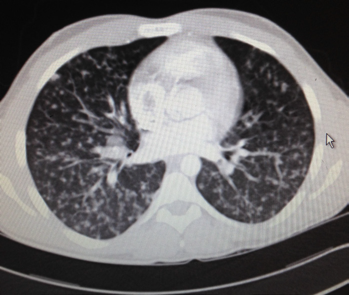

胸部影像学表现为结节状或间质性肺炎。两肺弥漫性结节,边缘清楚或模糊,结节周围可有GGO(磨玻璃影),也可表现为片状GGO,结节可有融合。

图4 21岁女性有水痘暴露史,表现为头痛、肌痛、关节炎、无力、咽痛与纳差,CT示两肺多发结节。(Shalaby T,et al. Br J Hosp Med (Lond). 2015)

图4 37岁既往体健男性因发热、干咳与胸部弥漫性皮疹2天就诊。

图5 同一病人,CT示两肺弥漫性GGO。(Miyokawa R, et al. J Gen Intern Med. 2019)

图6 25岁男性,因咯血急诊,3天前诊断水痘,被其3岁女儿传染,CT示两肺多发性边缘模糊的小叶中央型结节与伴外周GGO的微结节,以上叶为主。(Médart, L, et al. Varicella Pneumonia.)